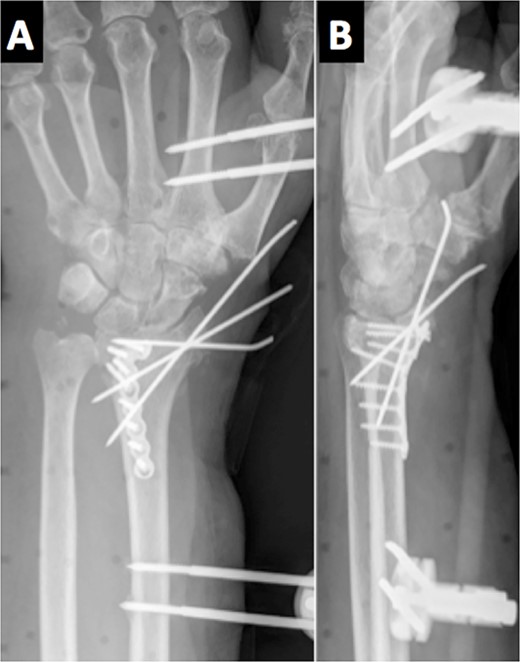

On the third month of follow-up, the loosening of the second most distal screw was observed on plain X-rays. Six months after surgery, radiographic controls showed a migrated screw lodged in the anterior aspect of the wrist. Moreover, the patient complained of anesthesia on the median nerve distribution of the hand (Fig. 3). No motor deficits or atrophy of the thenar eminence were noted. A standard electromyography (EMG) was performed resulting in a complete axonotmesis of the median nerve. During the following 8 months, the patient did not attend the follow-ups. Upon his next follow-up visit, the hypoesthesia on the radial three digits persisted despite the fact that no muscular atrophy or motor deficits were observed, as in his last clinical examination. A new EMG was performed again confirming complete median nerve axonotmesis, and with proximal stimulation, a Martin–Gruber anastomosis in the proximal forearm was discovered [4]. The patient refused further surgery for screw removal.

Radiological evidence of a migrated screw lodged in the anterior aspect of the wrist.